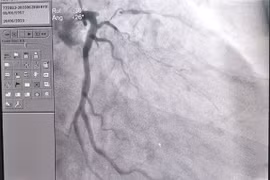

"Giờ vàng” trong điều trị nhồi máu cơ tim dùng thuốc tiêu sợi huyết trong vòng 2 giờ đầu sau khi cơn đau ngực xuất hiện. Trong vòng 12 giờ và hiện là 24 giờ cần khảo sát động mạch vành để đánh giá khả năng can thiệp.

Kỹ thuật Mini Crush là tái thông lòng mạch bị hẹp ở cả hai nhánh chính và phụ được tối ưu, giúp giảm triệu chứng đau ngực và suy tim ở bệnh nhân có tổn thương vị trí chia đôi của động mạch vành.